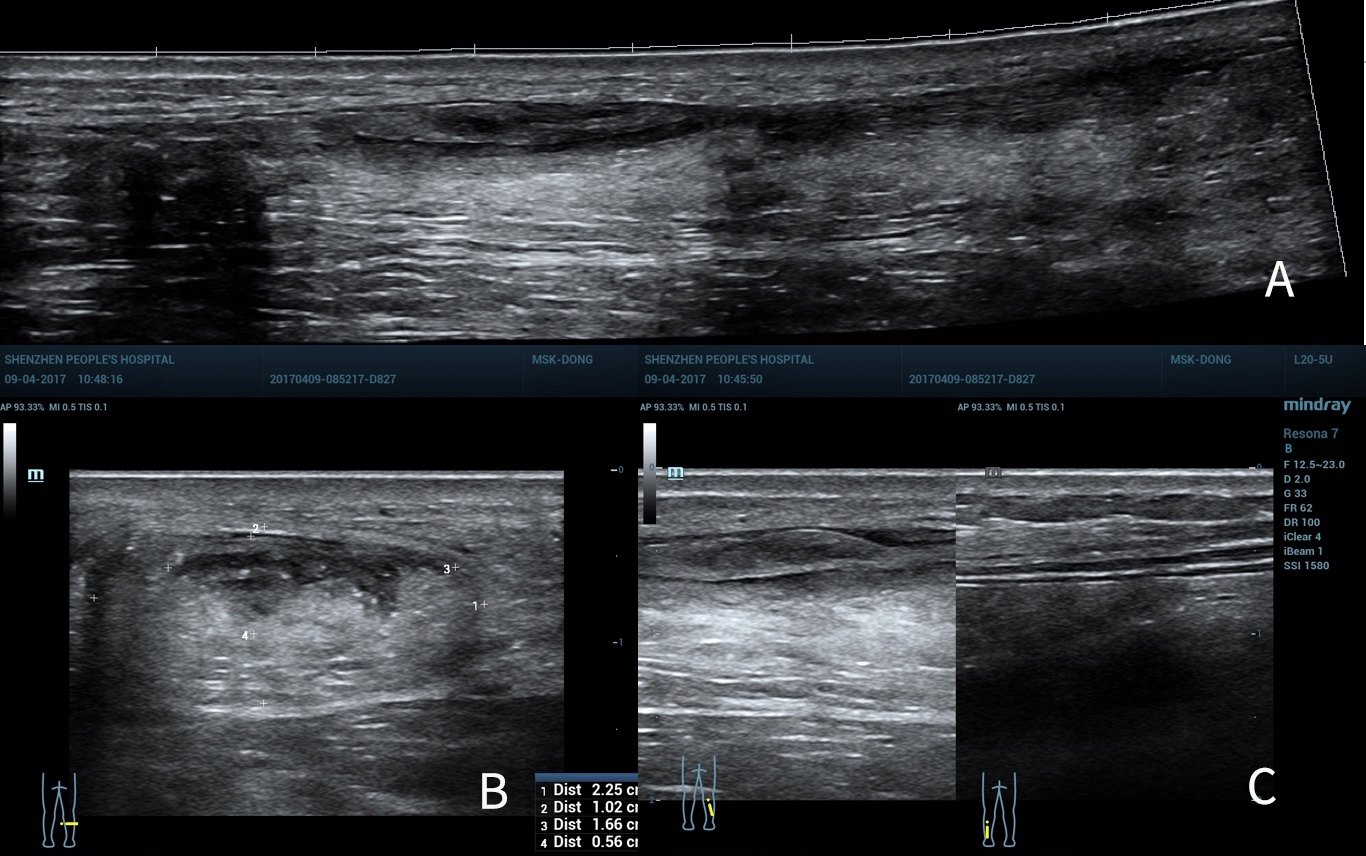

跖肌腱损伤 - 超声医学讨论版 -丁香园论坛

图片尺寸1170x649